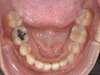

Avant

Après